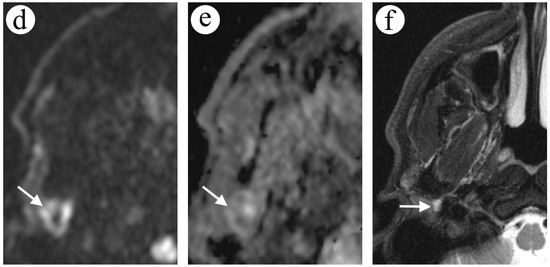

2.2. Case 2